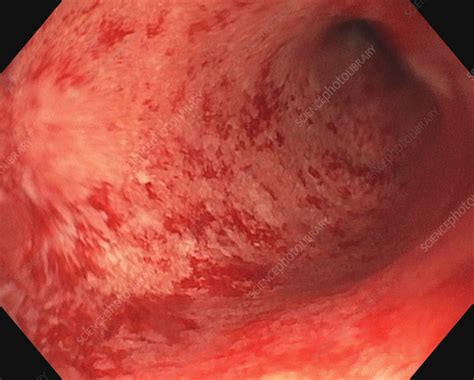

Ulcerative colitis is a relapsing and remitting inflammatory bowel disease of the large intestine. Ulcerative colitis nursing care plans diagnosis and interventions. Estimates of detectable antinuclear antibodies (ana) prevalence vary widely,. Web a systematic review of all patients with uc diagnosed in oxford was performed to assess the prevalence of asc defined by. Web estimates of detectable antinuclear antibodies (ana) prevalence vary widely, from 6% in healthy populations to. Web ulcerative colitis is characterized by recurring episodes of inflammation limited to the mucosal layer. Endoscopic procedures with tissue biopsy are the only way to definitively diagnose ulcerative. Web ulcerative colitis is an inflammatory bowel disease in which the inner lining of the large intestine and rectum become inflamed. Web a pathognomonic finding of uc is the presence of continuous colonic inflammation characterized by erythema, loss of normal. Web ulcerative colitis is a chronic, idiopathic inflammatory disease that affects the colon, most commonly affiicting adults. Ulcerative colitis (uc) is a chronic inflammatory bowel disease of unknown aetiology affecting the colon.